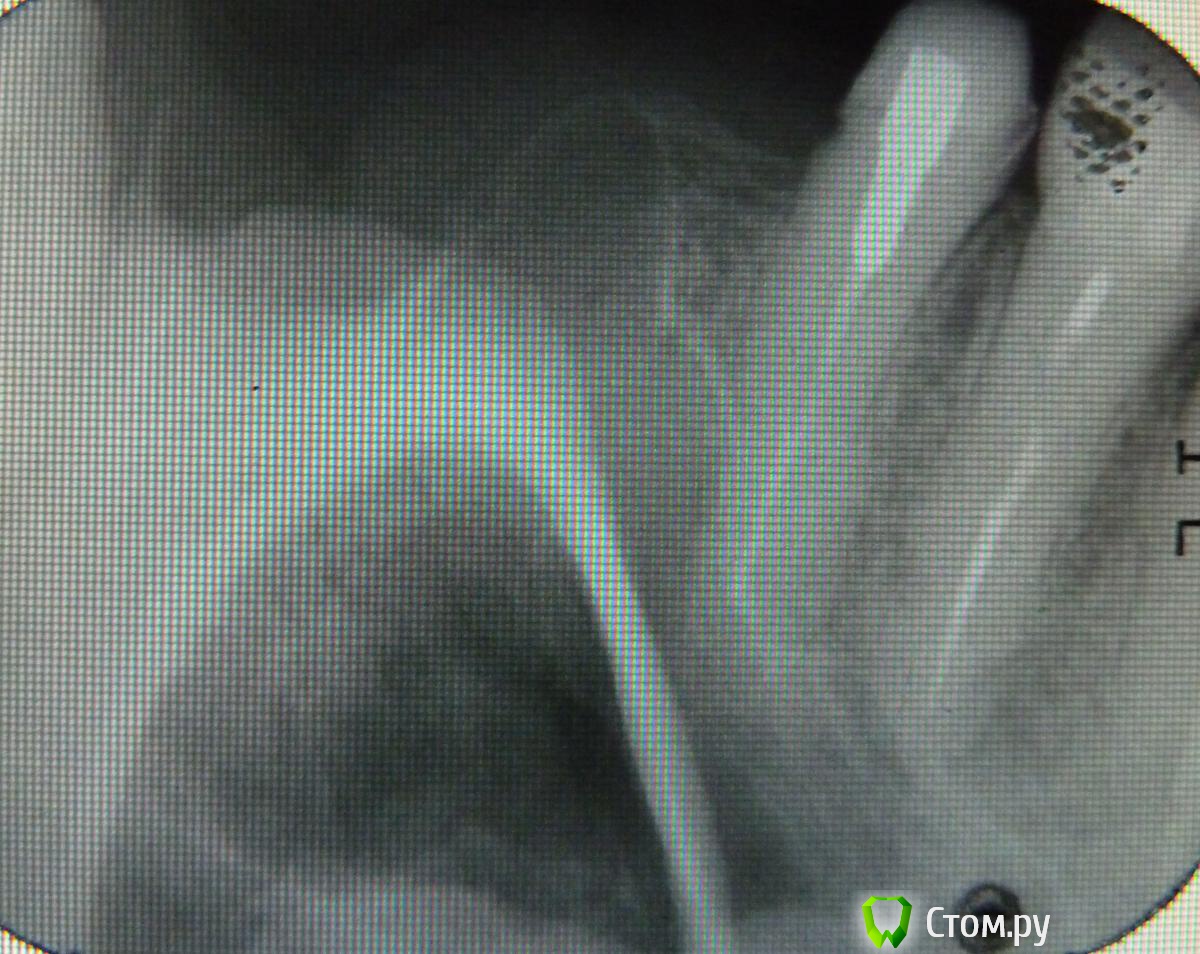

Робинзон Опубликовано 7 июня, 2014 Автор Поделиться Опубликовано 7 июня, 2014 Неделю назад удалили верхнюю 7-ку слева. Посмотрите, пожалуйста, все ли нормально.Зуб-3.jpgСпасибо.Вот другой снимок. Ссылка на комментарий

sydnik Опубликовано 7 июня, 2014 Поделиться Опубликовано 7 июня, 2014 похоже на кореньза 7 -ой еще зубы были? Ссылка на комментарий

Ирина Игоревна Опубликовано 7 июня, 2014 Поделиться Опубликовано 7 июня, 2014 снимок размытый, но скорее всего остался дистальный корень. Удаление было сложное?сейчас беспокоит? Ссылка на комментарий

IvanK Опубликовано 8 июня, 2014 Поделиться Опубликовано 8 июня, 2014 остался корень 1 Ссылка на комментарий